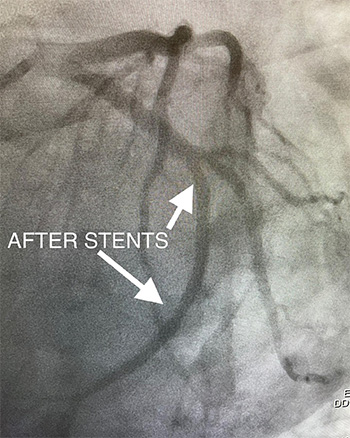

47y/o diabetic female with chest pain and dysrhythmia showing NSVT and slight elevation in Troponin. Coronary angiogram shows a severe eccentric 95% stenosis ( see BEFORE). She received a single DES stent in LAD with resultant resolution of the stenosis and excellent flow( see AFTER STENT). Her symptoms resolved after flow in the LAD was restored.